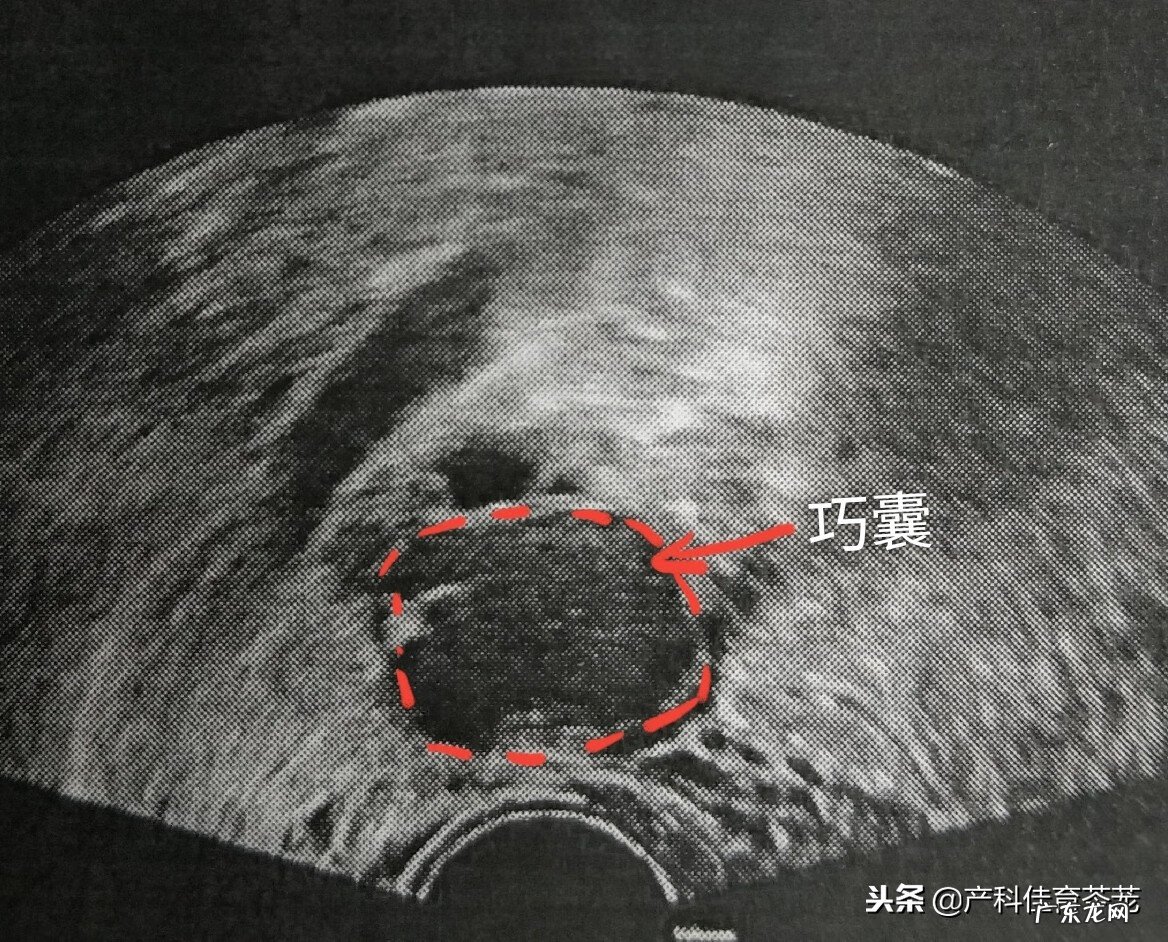

这种囊肿B超诊断准确率很高:

文章插图

同样里面是液体,但B超下看到的不是透亮的,里面有密集的细点状回声,说明不是单纯的一包“水”,而是有血 。